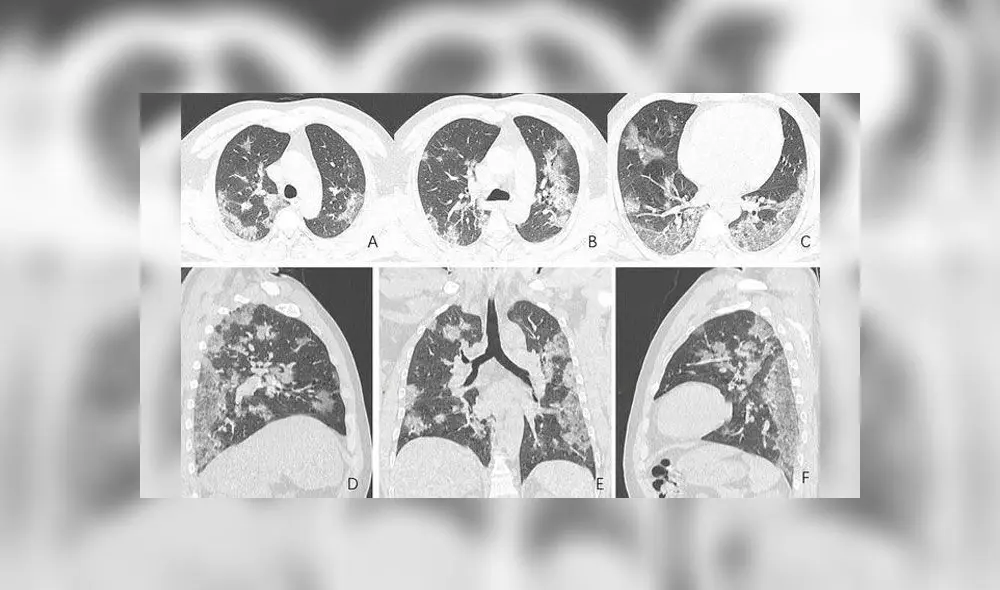

En un grupo de placas se observa la evolución de los pulmones de un hombre de 44 años, procedente de China, quien trabajaba en el mercado de mariscos de Wuhan, donde se cree que surgió el brote. Las tomografías muestran unas manchas blancas en las esquinas inferiores de dichos órganos, conocidas por los radiólogos como “opacidad de vidrio esmerilado”.

El hombre ingresó al hospital el 25 de diciembre pasado tras experimentar fiebre y tos por unas dos semanas, siendo diagnosticado con neumonía y síndrome de dificultad respiratoria aguda. Los escaneos grafican como, a medida que pasa el tiempo, el líquido en los mencionados espacios se hace más pronunciado.

Una semana después de su hospitalización, el individuo falleció.

Otro conjunto de imágenes computarizadas muestra el mismo llenado de espacios de aire en los pulmones de una mujer de 54 años, quien se infectó con coronavirus tras un viaje a Wuhan. Ella experimentó fatiga, tos, fiebre y congestión en el pecho, siendo luego diagnosticada con neumonía severa ocasionada por el COVID-19.